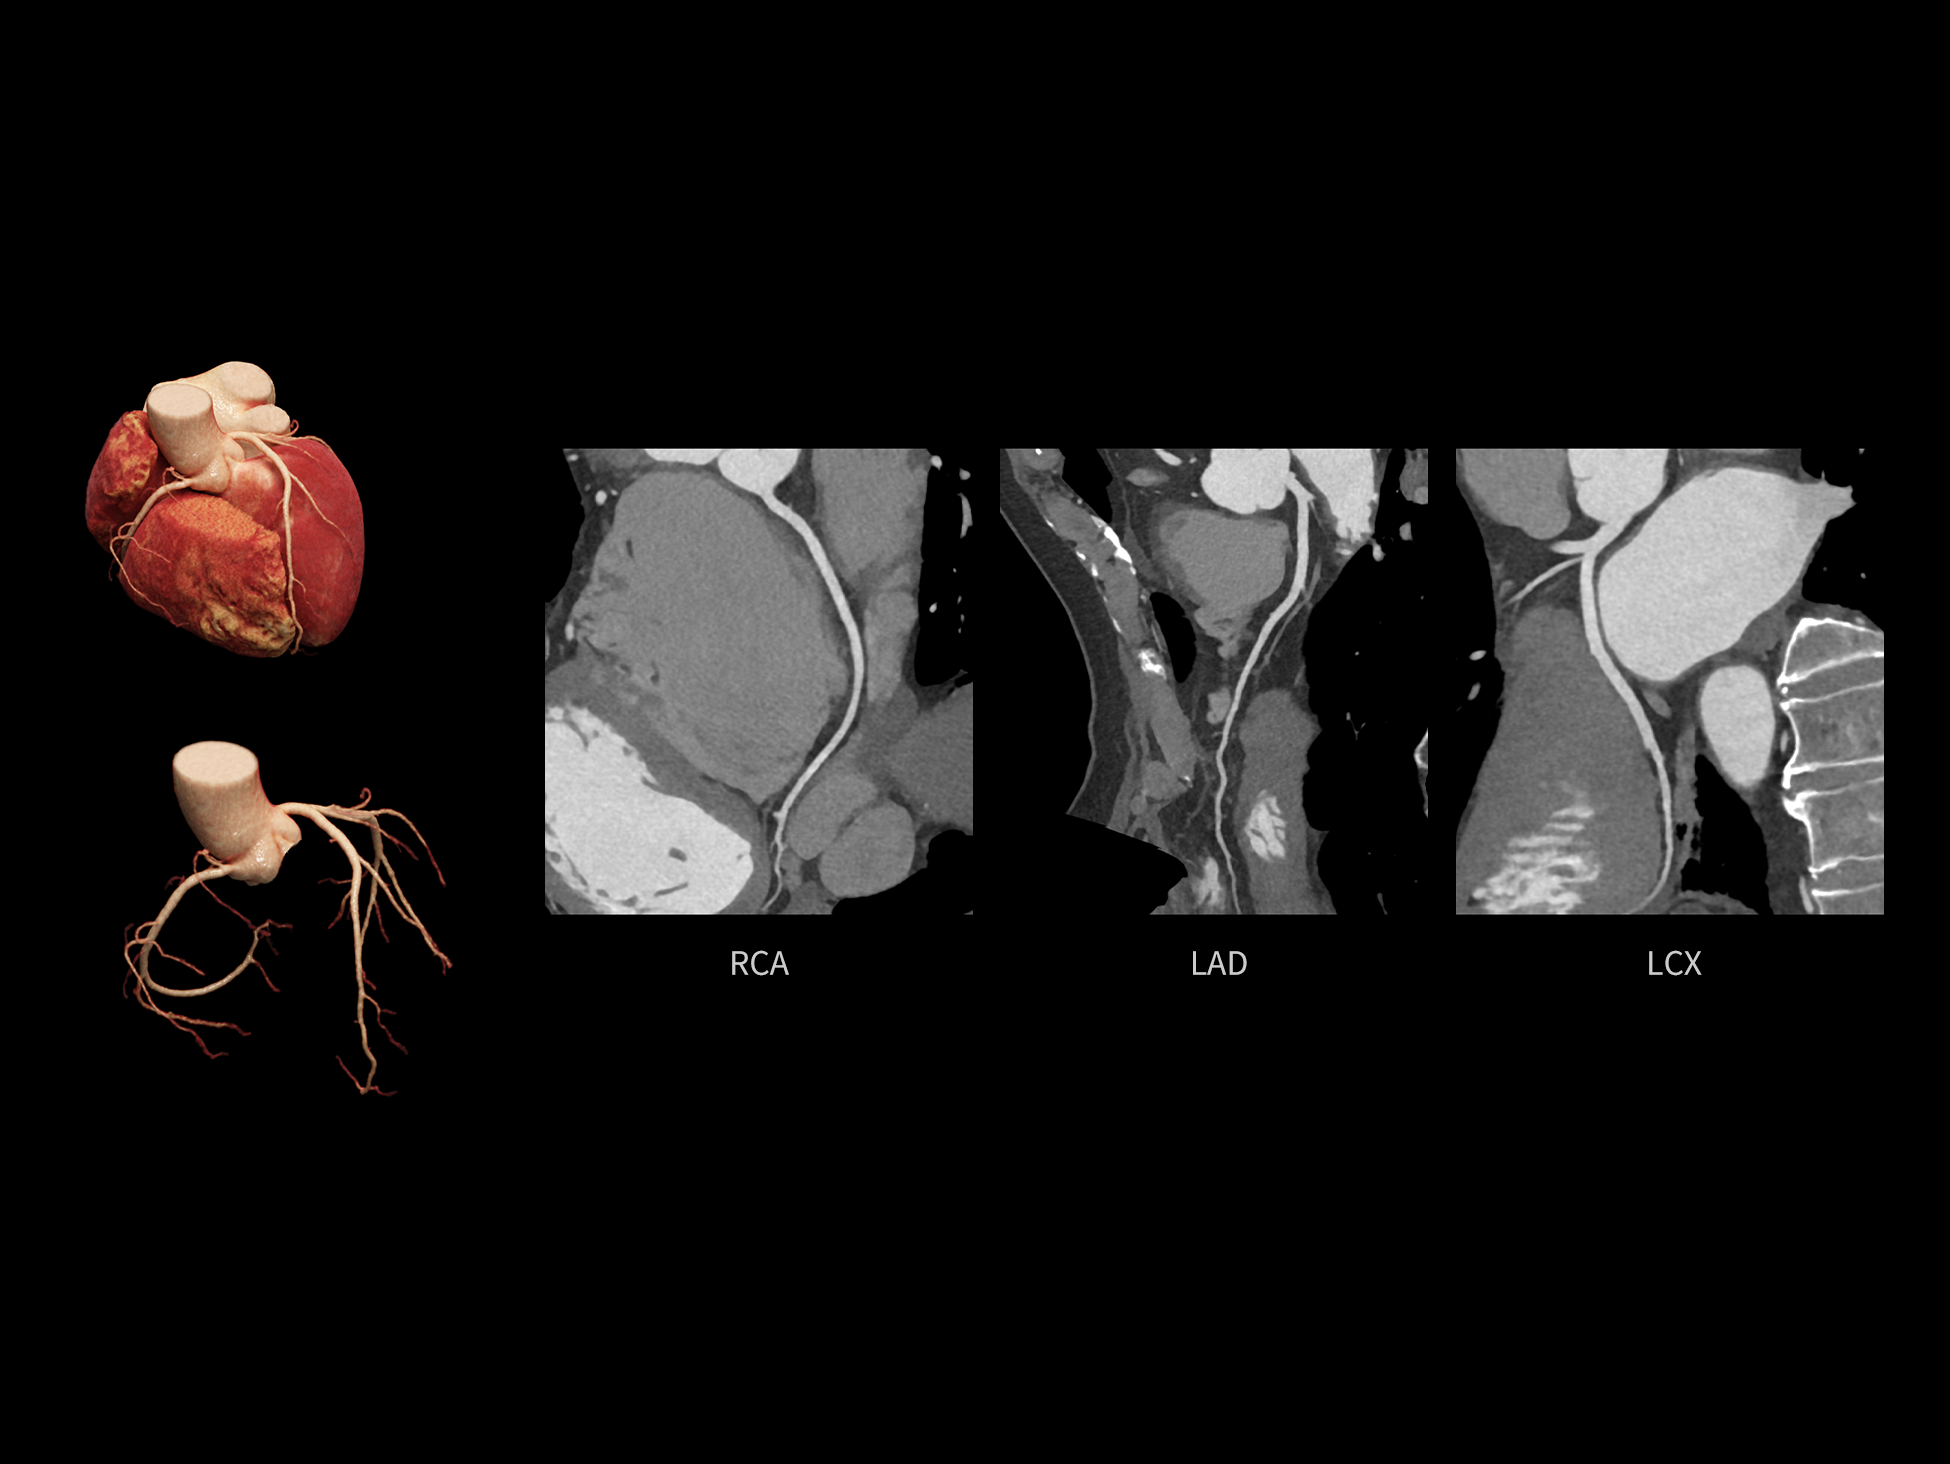

全时心脏

uCT SiriuX® 挑战心脏成像时间分辨率的极限,精准捕捉心脏全周期的动态变化。无论静态解剖形态,还是动态功能表现,都能清晰呈现,让心脏不再是“定格”的器官,而成为可视的生命律动。

全心结构运动校正

CardioCapture 2.0 可对心肌、瓣膜及心室等结构进行同步运动校正。基于深度学习的心脏精细分割,实现了更完整的心脏全局信息提取,能有效抑制全心运动伪影,显著提升心脏细节的清晰度与诊断可靠性。

心脏成像,自由掌控

uCT SiriuX® 以 8ms 全心等效时间分辨率与16cm宽体覆盖,突破传统心脏成像局限,完整呈现搏动中的心脏结构与动态功能;配合无心电门控扫描与智能化工作流,更使心脏检查摆脱心率、配合度与操作复杂度的束缚,实现真正自由从容的成像体验,为临床功能评估提供更深层依据。